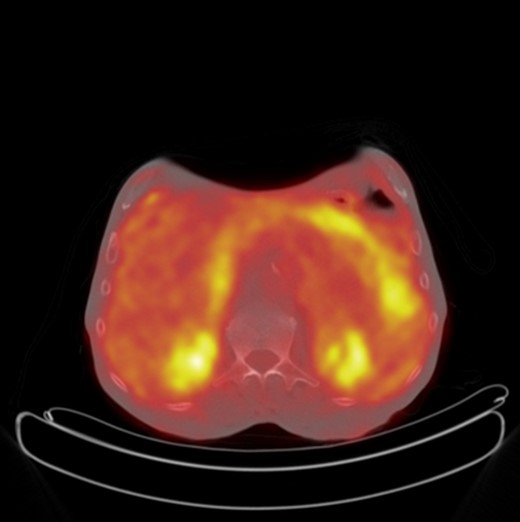

A 71-year-old male presented with a 10-month history of chronic diarrhoea, weight loss and left lower quadrant pain. He complained of increased frequency of bowel motions with up to 10 motions a day, abdominal pain and a weight loss of >10 kg. Three years previously he had undergone an extended right hemi-colectomy and adjuvant chemotherapy for a pT3 N1 M0 moderately differentiated adenocarcinoma in the transverse colon. His medical history was significant for hyperlipidaemia and ischaemic heart disease. His surgical history included diverticular disease with a previous diverticular perforation managed conservatively, bilateral total hip replacements and bilateral inguinal hernia repairs. In addition, he was a cigarette smoker of ∼80 pack-years. Clinical examination revealed no abdominal tenderness and no masses palpated per rectum. On further investigation, however, his serum carcinoembryonic antigen (CEA) level was noted to be elevated with a peak post-operative CEA of 14.8 g/dl when he presented 48 months after his initial surgical resection. Subsequent computed tomography (CT) of the thorax, abdomen and pelvis was negative for disease recurrence; however, an 18-fluorodeoxyglucose (18-FDG) positron emission tomography contrast-enhanced CT (PET/CECT) scan showed diffuse low-grade 18-FDG uptake within the mesenteric fat as well as near the site of the previous anastomosis, suspicious for peritoneal metastatic disease (Fig. 1). Repeat colonoscopy did not identify any luminal abnormality, and the decision was made to perform an elective diagnostic laparoscopy.

Axial PET CT showing increased FDG uptake in the mesentery of the left upper quadrant suspicious for metastatic recurrence.

Although this patient's follow-up endoscopy and CT imaging revealed no indication of disease recurrence, the PET CT showed areas of FDG uptake very suspicious for disease recurrence (Fig. 1). In a recent study of 69 patients by Ozkan et al., the sensitivity and specificity of 18F-FDG PET/CT in the detection of disease recurrence were calculated as 97 and 61%, respectively [8]. There was no correlation between patients' serum CEA levels and lesions' maximum standardized uptake values. Gauthe et al. reported PET/CECT's sensitivity and specificity in detection of tumour recurrence in colorectal cancer (CRC) patients with elevated CEA as 94.1 and 77.2%, respectively [9]. This patient's peak post-operative CEA was 14.8 g/dl when he presented 48 months after his initial surgical resection with his symptoms. As such, the decision to proceed with exploratory surgery was made because of the unfavourable results of the biochemical and radiological investigations.